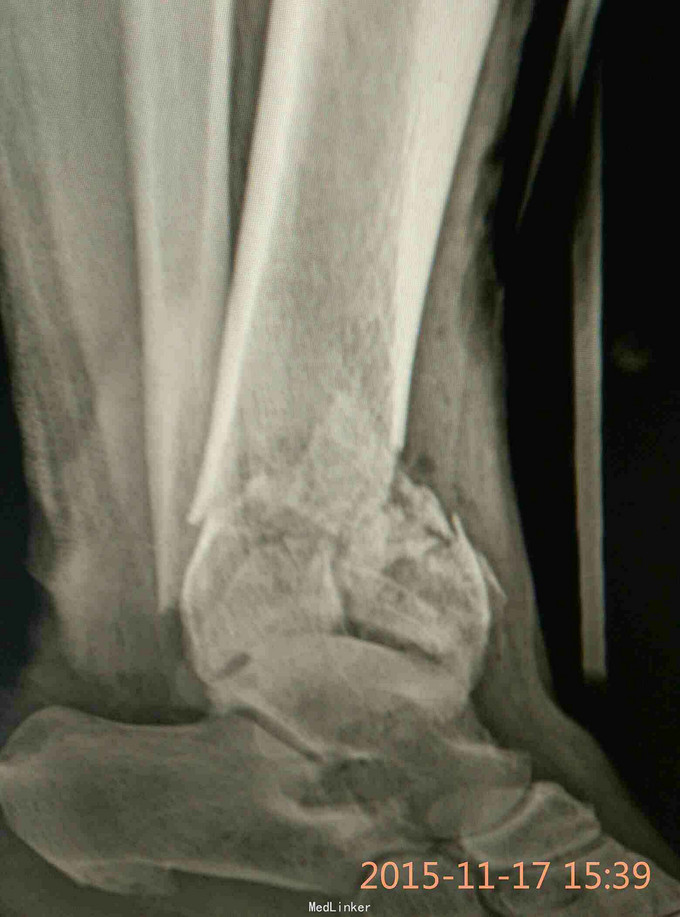

Pilon骨折,牵引10天

车祸致伤,开放性,急诊复位,跟骨牵引,清创,抗炎对症,伤口愈合可,无感染迹象,欲手术治疗,请各位老师给点建议。

伤时左踝畸形肿胀,外踝上方见长约5cm不规则裂伤,骨端外露,踝关节功能丧失,足背动脉搏动有力

左侧Pilon骨折于急诊清创骨折复位缝合并行跟骨牵引治疗。欲10天后,皮肤条件允许后,限期手术

选择何种术式,内固定物?